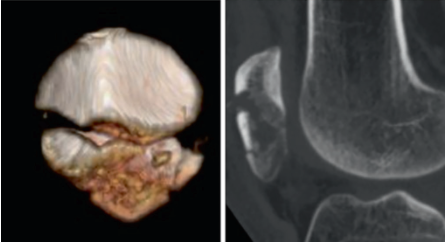

图1. 患者术前影像学检查示髌骨下极多发骨折,AO分型为C1.3;

(A) x线片正、侧位片;(C)髌骨三维重建;(D)矢状面断层图像显示远端碎片的细节。